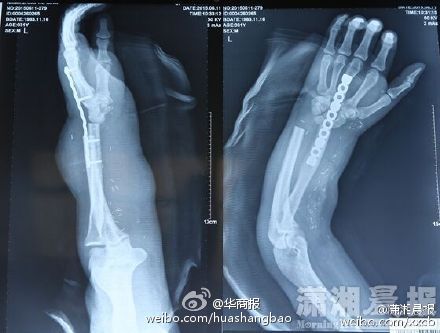

2015年7月17日,一则男子断手寄养在小腿的新闻在微博引起热议。把断掉手臂的手掌寄养的小腿上,并通过手术重新将手移植到男子手上,这个手术被不少网友称为现实版寄生兽。

在今年5月5日,湘潭周先生在车间操作设备时,其左手前手臂不慎被螺旋叶片绞断。为了重新让周先生的手掌重新再生,医生通过将其断手移植寄生在其小腿上。等到手掌恢复供血之后,再重新通过移植手术将手掌左前掌。

而在近日,周先生顺利的完成了手掌的移植手术,经过一段时间的调养,目前已经可以做轻微屈伸。